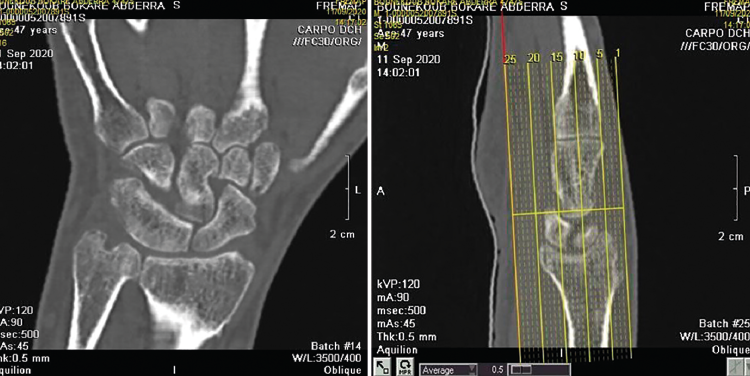

Figura 3. Imagen de resonancia magnética de muñeca y mano.